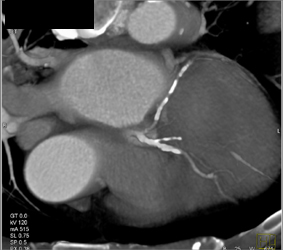

Huge Hiatal Hernia